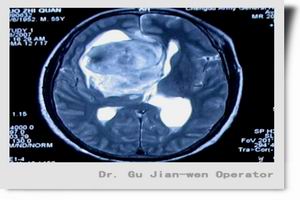

診斷檢查①大小形態正常;②球形對稱性擴大,深蝶鞍:深徑大於前後徑4.0mm以上;③呈杯形或四邊形。用CT檢查可發現約50%蝶鞍骨質侵蝕吸收。84.3%蝶鞍體積擴大。有的患者隨訪可見其體積進行性增大。垂體高度<4.0mm,其餘為水的密度,垂體柄延長進入垂體窩,有的垂體柄偏移或後移。全腦造影或造影劑可經鞍上池進入鞍內。

MRI檢查與CT的效果相仿,但可在橫、冠、矢3相檢查,腦脊液為更長T1及T2。

至於部分性或完全性空泡蝶鞍的CT診斷標準。Krysick依據106例下丘腦-垂體-卵巢軸功能缺陷的婦女,經CT測定垂體容積及凹入鞍內的蝶網膜疝的結果,提出垂體容積150mm3的影像改變可作為完全性空蝶鞍的診斷標準。

5.CT掃描及磁共振成像高分辨力的CT冠狀位掃描或磁共振成像能迅速而又無創傷地作出診斷。典型圖像示鞍窩擴大,垂體萎縮變形,被充滿與鞍上池同樣低密度的腦脊液取代。若作造影劑強化直接冠狀位CT掃描,則未見增強。重症患者垂體嚴重受壓,被推移至後下方呈薄片狀,垂體柄可深達鞍底,形成特徵性的“漏斗征”(infundibulum)。